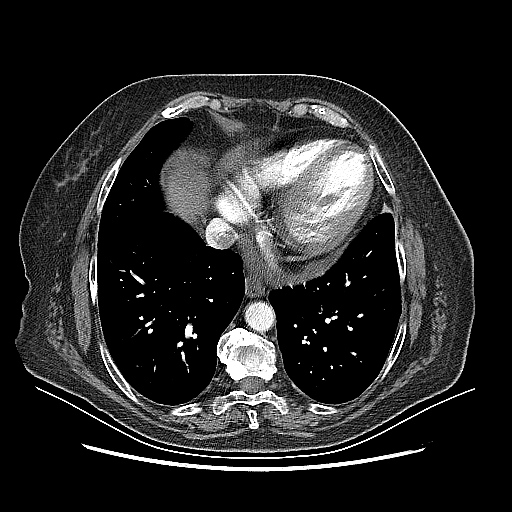

Original VENOUS CT scan

No window - Raw intensity values

Lung window (WL -600, WW 1500 β†’ Low βˆ’1350, High +150)

Mediastinum window (WL 40, WW 400 β†’ Low βˆ’160, High +240)